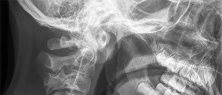

A 25-year-old male is involved in a high-speed motor vehicle collision. Radiographs demonstrate a traumatic spondylolisthesis of the axis (Hangman's fracture) with an oblique fracture line through the pars interarticularis, minimal translation, but extreme angulation (>11 degrees). The C2-C3 disc space appears disrupted posteriorly. According to the Levine-Edwards classification, what is the most appropriate initial management for this specific injury pattern (Type IIa)?

The scenario describes a Levine-Edwards Type IIa Hangman's fracture. This injury is caused by a flexion-distraction mechanism, leading to severe angulation with minimal initial translation. A critical point in management is that axial traction is STRICTLY CONTRAINDICATED, as it will exacerbate the distraction and worsen the deformity. The appropriate non-operative management involves the application of a halo vest under gentle compression and extension to reduce the angulation and stabilize the fracture.